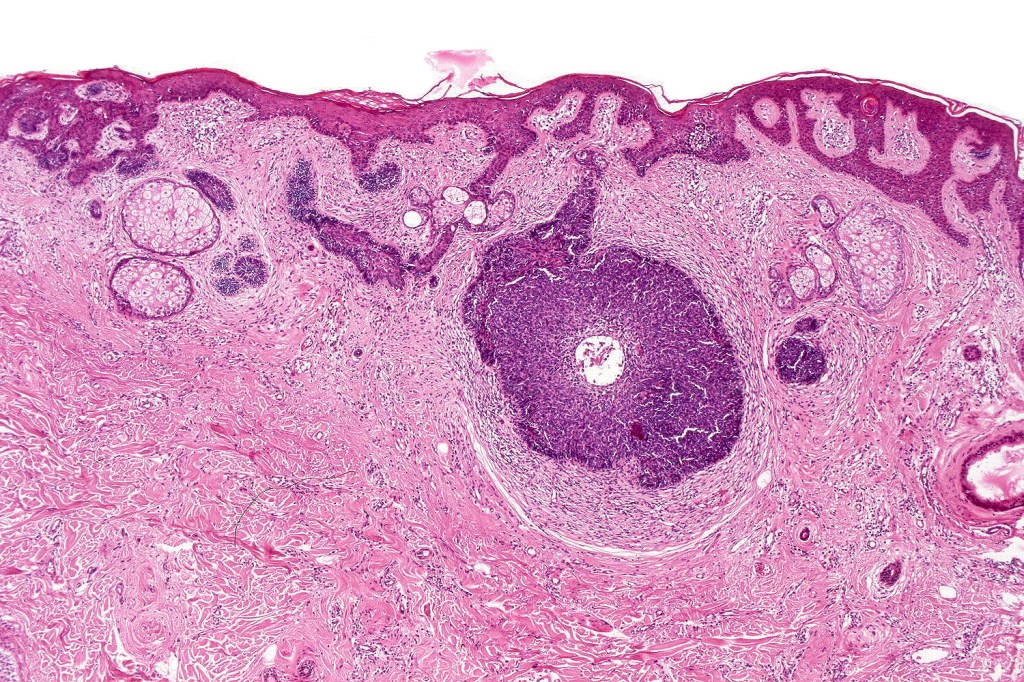

•May be complicated by a wide range of tumors (which are often multiple) including trichilemmoma, trichoblastoma, SCAP, sebaceous tumors, sweat gland tumors, melanocytic nevi & rarely by malignant tumors including BCC, SCC, melanoma, trichilemmal carcinoma, apocrine carcinoma & microcystic adnexal carcinoma

•Follicular induction is common & sometimes trichoblastomatous foci are evident